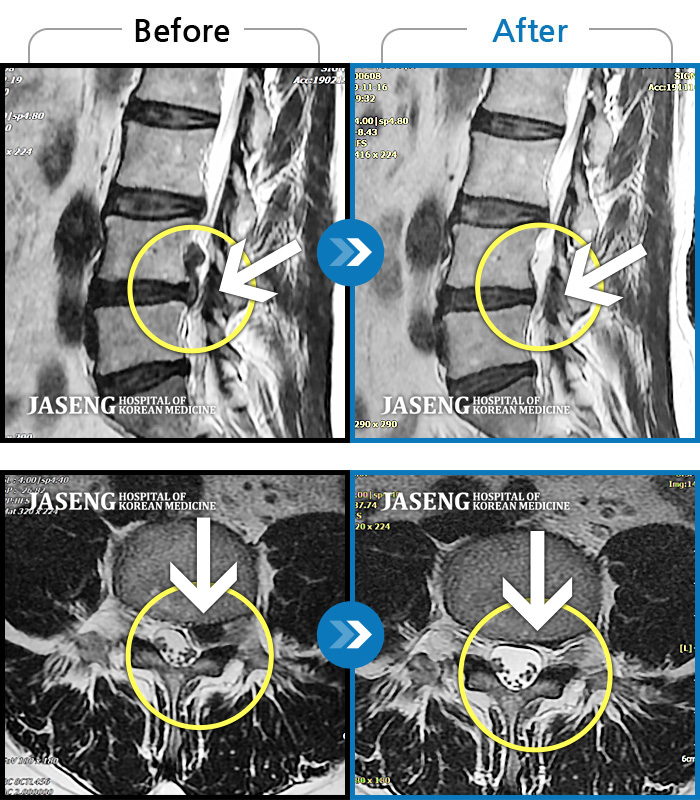

Before

After

환자에게 사전 동의를 받아 동일 조건에서 촬영되었습니다.

개인에 따라 치료 후 부작용이 발생할 수 있으니 의료진과 상담 후 치료를 진행하시기 바랍니다.

양측 허리와 골반 통증, 양측 다리 저림

우측 허리와 골반 통증, 우측 다리에 통증과 저림